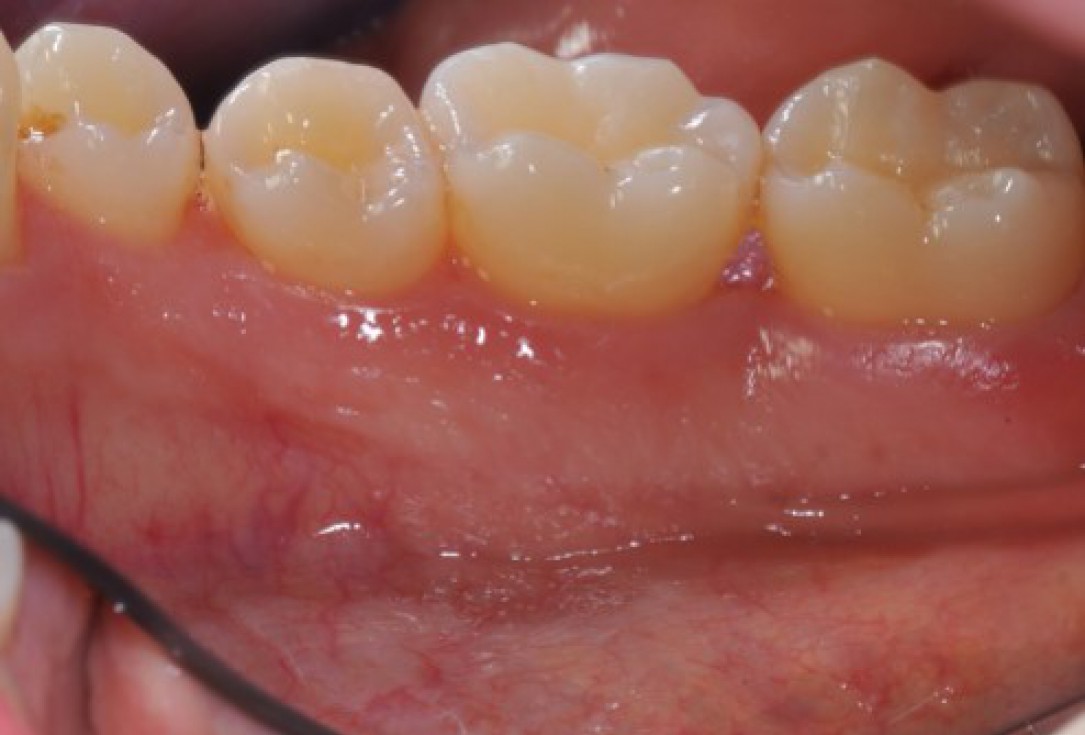

02/22 - Pre-surgical clinical situation, lingual view.

Deep intrabony defects treated using Straumann® Emdogain® - Dr. M. Stefanini